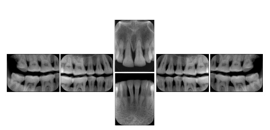

Intra-oral radiography typically involves acquisition of multiple images of various parts of the dentition. Many digital radiographic systems offer customized templates that are used for displaying the images in a study on the screen. These templates may also be referred to as mounts or view sets. The Structured Display Object represents a standard method of encoding and exchanging the layout and intended display of Structured Displays. A structured display object created in this manner could be stored with a study and exchanged with images to allow for complete reproduction of the original exam.

2. A patient requests cosmetic surgery to enhance their facial appearance. The case requires consultation between an orthodontist in New York and an oral surgeon in California. The cephalometric series of 2D projections constructed from a volumetric CT data set that is used for the discussion is arranged by a Structured Display for transfer between the two practitioners.

Cephalometric Series Structured Display

Figure OO-2. Cephalometric Series Structured Display

3. A dental provider wishes to capture a series of DICOM IO images for the patient’s dentition. The tooth morphology, teeth are divided into molars, premolars, canines and incisors, and a number of images for each jaw. The anatomic information was captured utilizing the triplet of schema. This standard code sequence is based on ISO 3950-2010, Dentistry - Designation system for teeth and areas of the oral cavity.

Every IO image should have anatomic information either through the primary or modifier sequence.

In most standard cases, images are oriented in structured layouts. These structured displays are useful to be shared between providers for reference purposes.

Table OO.1.1-1 shows structured display standard templates, where Viewset ID is based on the Japanese Society for Oral and Maxillofacial Radiology (JSOMR) classification provided by JIRA (Japan Medical Imaging and Radiological Systems Industries Association, www.jira-net.or.jp). Expected or typical teeth to be imaged location, region and designation codes are based on ISO 3950-2010, Dentistry - Designation system for teeth and areas of the oral cavity. For all the hanging protocols listed in OO.1.1-1, the value to use for Hanging Protocol Creator (0072,0008) is "JSOMR" and the value to use for Hanging Protocol Name (0072,0002) does not include "JSOMR" (e.g., "DL-S001A", not "JSOMR DL-S001A").